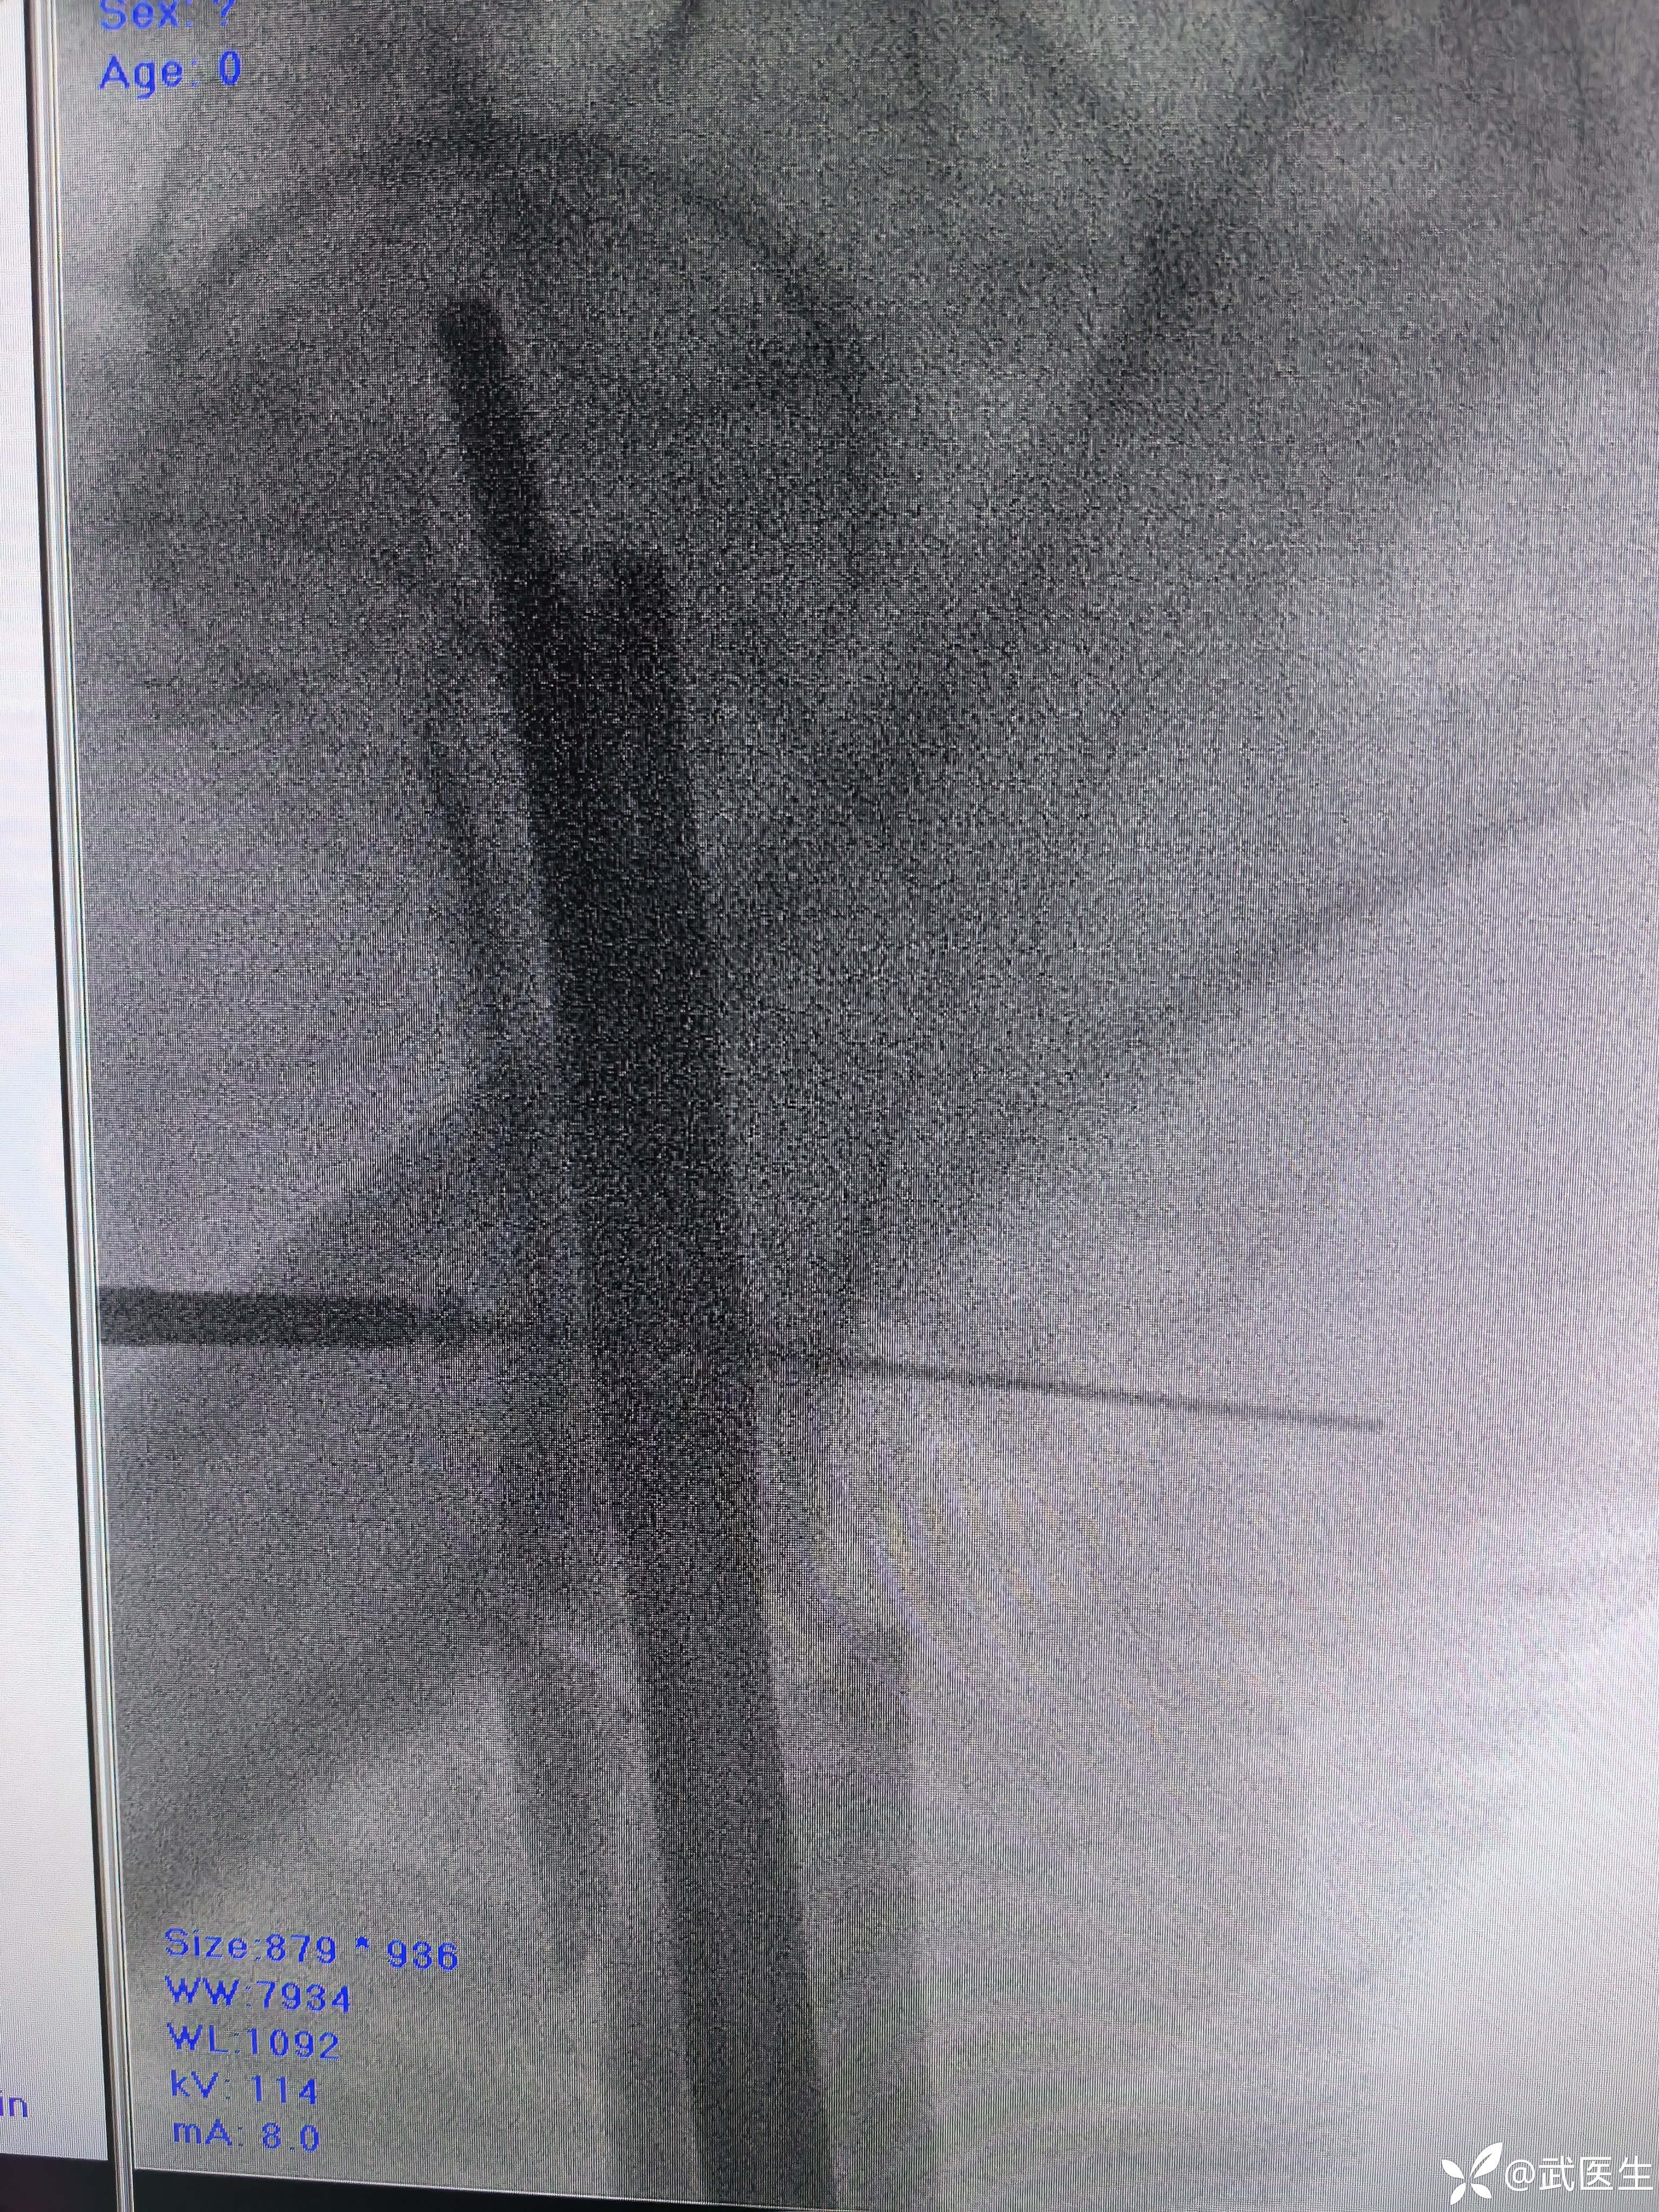

常规侧卧位,定位

合适入针点,开口,对位差,手法复位

利用金手指置入导针,扩髓,步骤省略